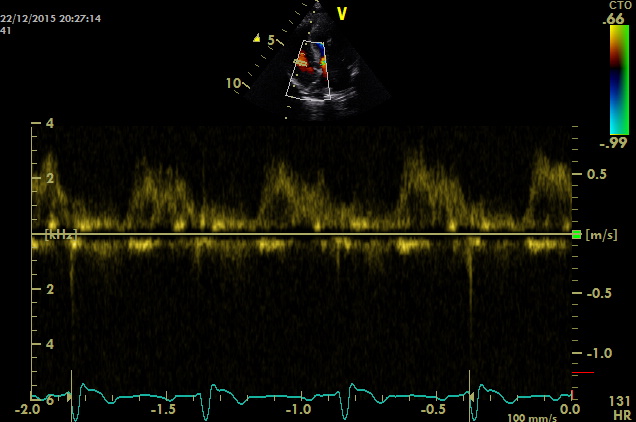

come si puo’ notare dai particolari nelle immagini zoom la struttura valvolare appare integra con una normale conformazione delle cuspidi la turbolenza e’ generata da una piccola banda fibrosa sottovalvolare ,in questo caso a dispetto delle alterazioni minime visualizzabili nell’esame B mode la stenosi sulla base del gradiente appare severa ,il PHT inferiore ai 300mm/sec dell’insufficienza aortica che quasi sempre accompagna la stenosi indica pressioni diastoliche nel ventricolo sx elevate

I difetti possono coesistere in questo caso la polmonare e’ normale ,nei primi video si ha la sensazione che coesista un DIV (flusso in avvicinamento concomitante la sistole tuttavia le differenze di gradiente sono troppo elevate tra camera destra e sx dovrebbe generarsi turbolenza che non si vede ,il soggetto deve essere comunque ricontrollato .

In questo caso la somministrazione di beta bloccanti non ha impedito il decesso che e’ avvenuto tre mesi dopo la diagnosi. (pazienti con questi gradienti muoiono entro l’anno di vita).